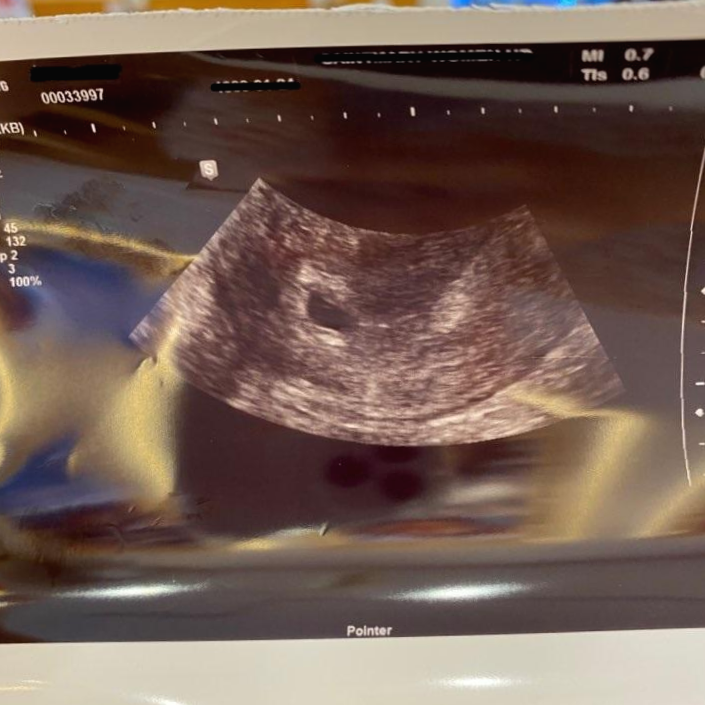

병원을 가서 접수를 하고 초진을 받고 좀 기다리니 담당 의사분께 초음파를 보게됐어요.

의사 선생님이 바로 "축하합니다!!"하고 환하게 웃으면서 말씀해 주시더군요;;;

초음파를 보여주시면서 아기집이 아주 잘 자리잡았다고 5주 0일 됐다고 하시더라고요.

저도 처음 병원에 가서 아기집을 확인한 후에 의사 선생님이 축하한다고는 하셨지만 이제 조심해야한다며 몇 가지 주의사항을 알려주셨어요. 지금 5주가 되어 아기집이 생겼지만 지금은 약 70%정도 임신 확정이라고 하셨었거든요. 나머지 30%정도는 이렇게 아기집을 확인하고도 임신 초기에는 유산이 되는 경우가 많이들 있다고 하더라고요.

아기집이 생성되었지만 엄마 아빠의 염색체가 맞지 않아 아기가 되지 못하는 경우와 또한 아기가 생겼지만 추후 초음파에서 아기의 심장이 뛰지 않는 경우 등도 임신 초기에는 더러 있다고 했어요.